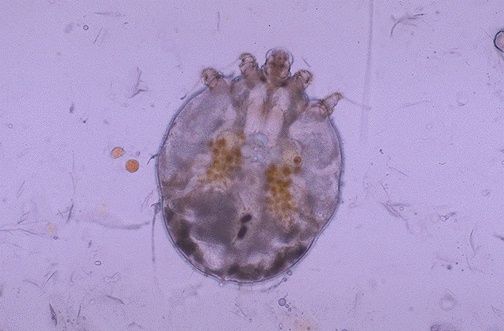

Scabia - Raia